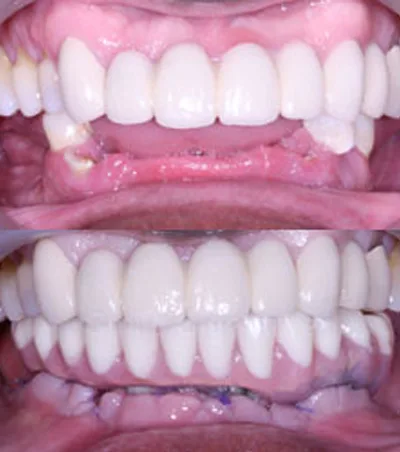

การฝังรากแบบนี้เป็นวิธีที่ทำกันโดยทั่วไป สามารถทำได้เกือบทุกกรณี สามารถฝังรากฟันเทียมชนิดนี้เพื่อทดแทนฟันที่สูญเสียไปเพียงซี่เดียว หลายซี่ หรืออาจจะทั้งปาก

โดยปกติแล้วการฝังรากฟันเทียมแบบทั่วไปนั้นแบ่งออกเป็น 2 ขั้นตอน ระยะห่างแต่ละขั้นตอนนั้นห่างกันประมาณ 2-6 เดือน

การฝังรากฟันเทียมแบบทั่วไปสามารถทำได้ในสภาพกระดูกขากรรไกรของคนไข้ส่วนใหญ่ แต่หากในบางกรณีที่คนไข้กระขากรรไกรมีความบางกว่าปกติ หรือมีการสูญเสียกระดูกบริเวณที่จะทำหารฝังรากฟันเทียม ทันตแพทย์เฉพาะทางอาจพิจารณาให้ปลูกกระดูกก่อนรับการฝังรากฟันเทียม เพื่อให้กระดูกบริเวณนั้นมีความหนา และแข็งแรงพอรองรับการฝังรากฟันเทียม